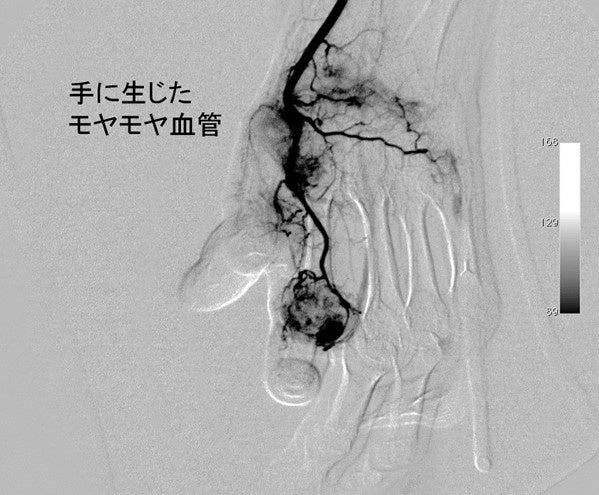

動注治療は、痛みの発生部位にできる異常な血管、つまり『モヤモヤ血管』を減少させる画期的な治療法です。

最近の研究により人間の身体には正常な血管だけでなく、痛みの原因になってしまうモヤモヤ血管ができてしまうことが分かってきました。これらのモヤモヤ血管と一緒に神経もできてしまうため痛みが生じます。